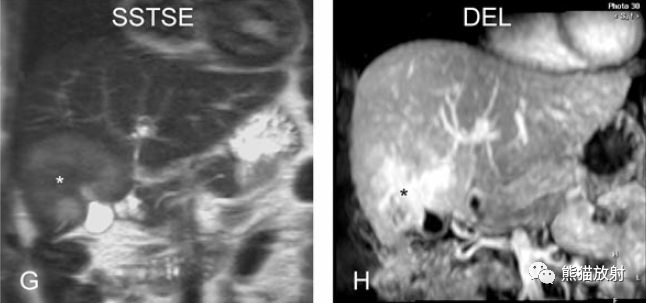

膽囊壁水腫

Gallbladder Wall Edema

膽囊壁增厚(并肝硬化、門脈高壓、腹水)。T2WI顯示膽囊壁因水腫而光滑均勻增厚,增強(qiáng)延遲期顯示強(qiáng)化的膽囊壁(內(nèi)外兩層:粘膜層和漿膜層),薄而清晰光滑。